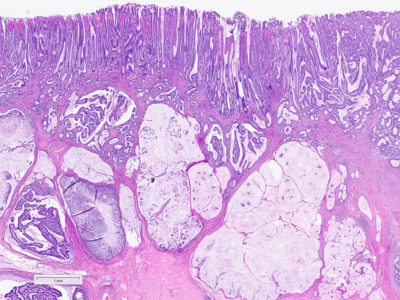

A 92-year-old man diagnosed with gastric cancer underwent a partial gastrectomy. On gross examination, the specimen measured 11×6 cm and a 4.5 cm tumour was identified 2 cm from the distal margin within the antrum.

Histologically, the tumour was confirmed to be an adenocarcinoma invading through the gastric submucosa into the muscularis propria (Panel A), showing multiple architectural patterns. While the majority of the lesion displayed a tubular and papillary arrangement of neoplastic cells (Panel B), there were also mucin pools containing floating tumour cells (Panel C), as well as areas of discohesive signet-ring cells (Panel D), so called for their intracytoplasmic mucin droplet that eccentrically displaces the nucleus. The different architectural patterns were not entirely independent of each other nor were they intermingled, but rather arranged side by side (Panel E).